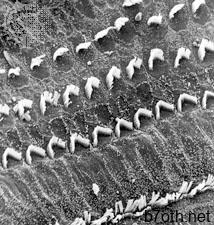

أكثر أهمية من علاج تلف الأعصاب السمعية هو الوقاية. حالات الصمم عند الوليد بسبب يمكن تجنب الحصبة الألمانية (الحصبة الألمانية) في الأم باستخدام لقاح الحصبة الألمانية. يمكن تجنب التلف العصبي الناجم عن التعرض لضوضاء مفرطة وطويلة عن طريق الاكتشاف المبكر. تتمثل إحدى الطرق في تقديم اختبارات سمعية روتينية للأفراد الذين يعملون في بيئات لا يمكن تجنب الضوضاء المفرطة فيها.